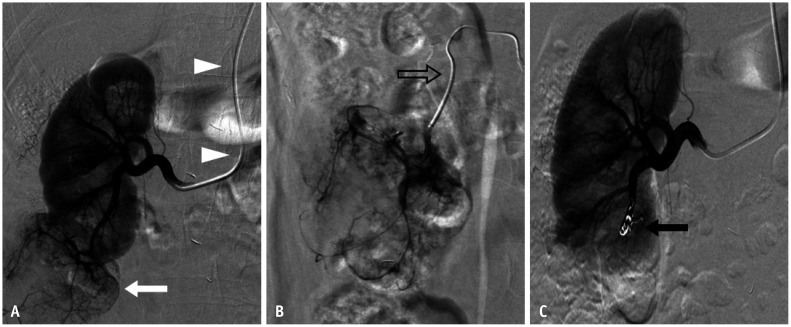

Abstract Image